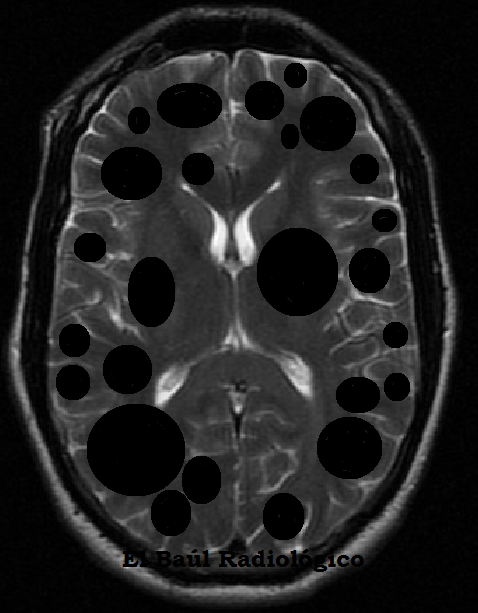

El Baúl Radiológico: METÁSTASIS ENCEFÁLICAS MÚLTIPLES, DE ... 😈